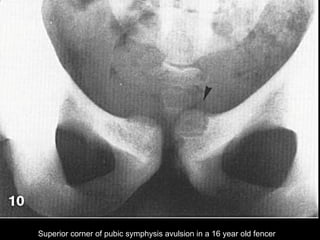

Superior corner of pubic symphysis avulsion in a 16 year old fencer